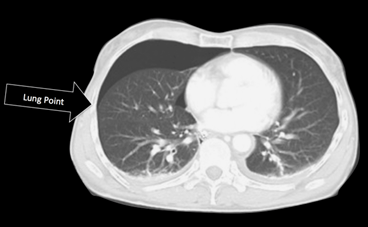

Medmindre der er tale om en komplet kollapset lunge vil der ved pneumothorax være områder hvor pleura viscerale er i kontakt med pleura parietale (FIGUR 6). I disse områder ses fortsat bevaret lung sliding i forbindelse med vejrtrækning. I områder hvor pleurabladene er adskilt grundet pneumothorax vil lung sliding ikke kunne visualiseres og pleuralinjen vil fremstå statisk. Med ultralydscanning kan stedet hvor pleurakontakten ophører visualiseres. Overgangen mellem lung sliding og ophørt lung sliding benævnes lung point. Erkendelse af et lung point er forbundet med en specificitet omkring 98% og betragtes som diagnostisk for pneumothorax[5, 6].

Figur 6: En CT-scanning med højresidig pneumothorax. Bemærk at luften (sort) samler sig ventralt. Dorsalt for midtaxillærlinjen er der fortsat kontakt mellem lungehinderne. Området hvor kontakten ophører kaldes lung point og kan erkendes med FLUS.